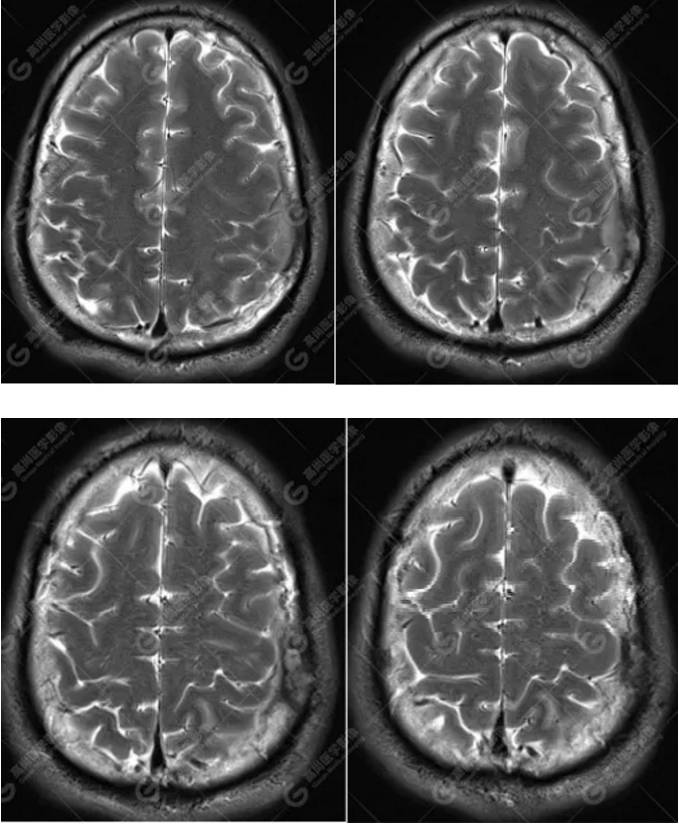

MR圖像

左側(cè)額頂部顱骨骨質(zhì)破壞并相鄰硬腦膜增厚強(qiáng)化,考慮Rosai Dorfman?。≧DD)可能,需與朗格漢斯細(xì)胞組織細(xì)胞增生癥鑒別。

典型的RDD在MRI上T1WI 呈等信號(hào),T2WI及 DWI為等-低信號(hào),增強(qiáng)掃描多為明顯均勻強(qiáng)化,多伴有腦膜尾征,部分病例伴有不同程度的腦水腫。T2WI 像 RDD 病灶中出現(xiàn)聚集的低信號(hào)影及 CT檢查沒有鈣化是 RDD 的特征性影像學(xué)表現(xiàn)。